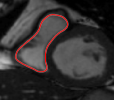

Figures 8 and 9 shows some sample tracking results of the proposed method and Medviso on full cardiac cycles of two different cases on both the LV dataset and the RV dataset. The ground truth (yellow) is superimposed when available. A summary of the results on the entire datasets is shown in Table I. The accuracy with respect to ground truth is measured using average perpendicular distance (APD) and dice metric (DM) for left ventricle, and Hausdorff distance (HD) and DM for the right ventricle. These metrics are chosen since they are the standard ones used on these datasets. Both qualitative and quantitative results show that our proposed method leads to more accurate segmentation of the ventricles and thus leads to less interaction than segmentation propagation schemes in than Medviso.

|

Medviso

![]() |

our method